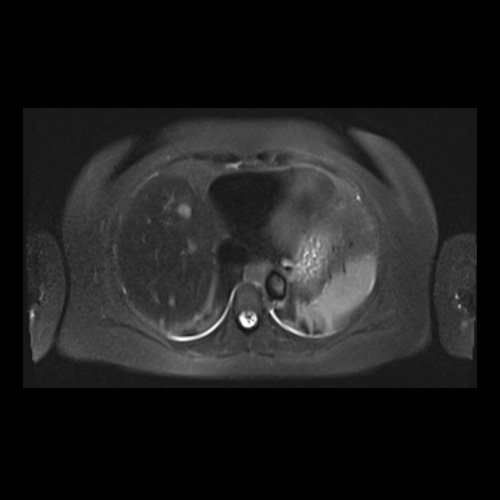

RMN de abdomen con contraste endovenoso (14/02/26) Corte axial (T2): múltiples lesiones sólidas de distribución difusa, levemente hiperintensas.

RMI abdomen y pelvis con contraste EV (14/02/26): En las bases pulmonares se visualizan atelectasias laminares bibalsales. No se identifica derrame pleural. El hígado es de forma, tamaño y situación normal. La superficie es lisa, los bordes son agudos. Se observan múltiples lesiones sólidas de distribución difusa, levemente hiperintensas en T2, con restricción en difusión y realce homogéneo tras la administración de contraste EV, la de mayor tamaño de 15 mm en segmento VII. Sugiero conocimiento histológico. La vía biliar intra y extrahepática es de calibre conservado. La vesícula biliar es de forma y situación habitual, sus paredes son finas y no presenta imágenes hipointensas en su interior, que sugieran la presencia de litiasis. El bazo es de forma, tamaño y situación normal, sin efectos de masa focales. El páncreas es de forma, tamaño y situación normal, sin efectos de masa. El Wirsung es de calibre conservado. Glándulas adrenales de forma, tamaño y situación normal, sin efectos de masa. Ambos riñones son de forma, tamaño y situación normal, con adecuada diferenciación córtico subcortical. No se observan alteraciones a nivel de la vía excretora. No se observan adenomegalias retroperitoneales ni intraperitoneales. La aorta abdominal, las arterias iliacas primițivas, internas, externas y femorales son de trayecto y calibre normal La vena cava inferior, las venas ilíacas primitivas, internas, externas y femorales son de trayecto y calibre normal. No impresionan alteraciones a nivel del tracto gastrointestinal. La vejiga es de paredes finas, normalmente distensibles, sin evidencia de lesiones endoluminales ni parietales. Mioma transmural en hoja anterior de útero que mide 55 x 47 mm sin signos de complicaciones. Imagen ovalada de contenido líquido que mide 65 x 52 mm en el espesor del tejido celular subcutáneo de región antero-superior de muslo derecho, por delante de músculo sartorio, que no presenta realce tras la administración de contraste EV.